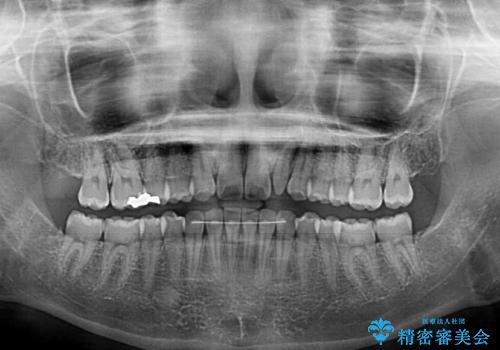

- 1年後に海外に転居するため、気になる前歯を矯正治療で整えたいとのことで来院された患者様です。

下顎は叢生が強かったため、奥歯までワイヤーを装着し、上顎は前歯の一部のみ気になっていたので、その部分にだけワイヤー装置を装着することとしました。